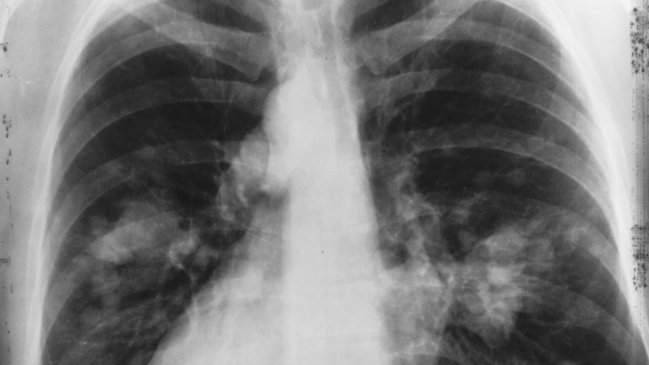

Un grupo de investigadores españoles descubrió un nuevo tratamiento para reducir el cáncer de pulmón, que ha resultado efectivo en 80% de los pacientes analizados.

El hallazgo del Grupo Español de Cáncer de Pulmón (GECP) fue presentado en el congreso mundial de esta patología en Barcelona y se trata de una fórmula basada en quimioterapia e inmunoterapia.

El tratamiento, aplicado a pacientes en estado intermedio de la enfermedad, consiste en agregar por vía intravenosa un medicamento oncológico y, 18 meses después, la mayoría de las personas analizadas estaba libre del cáncer.